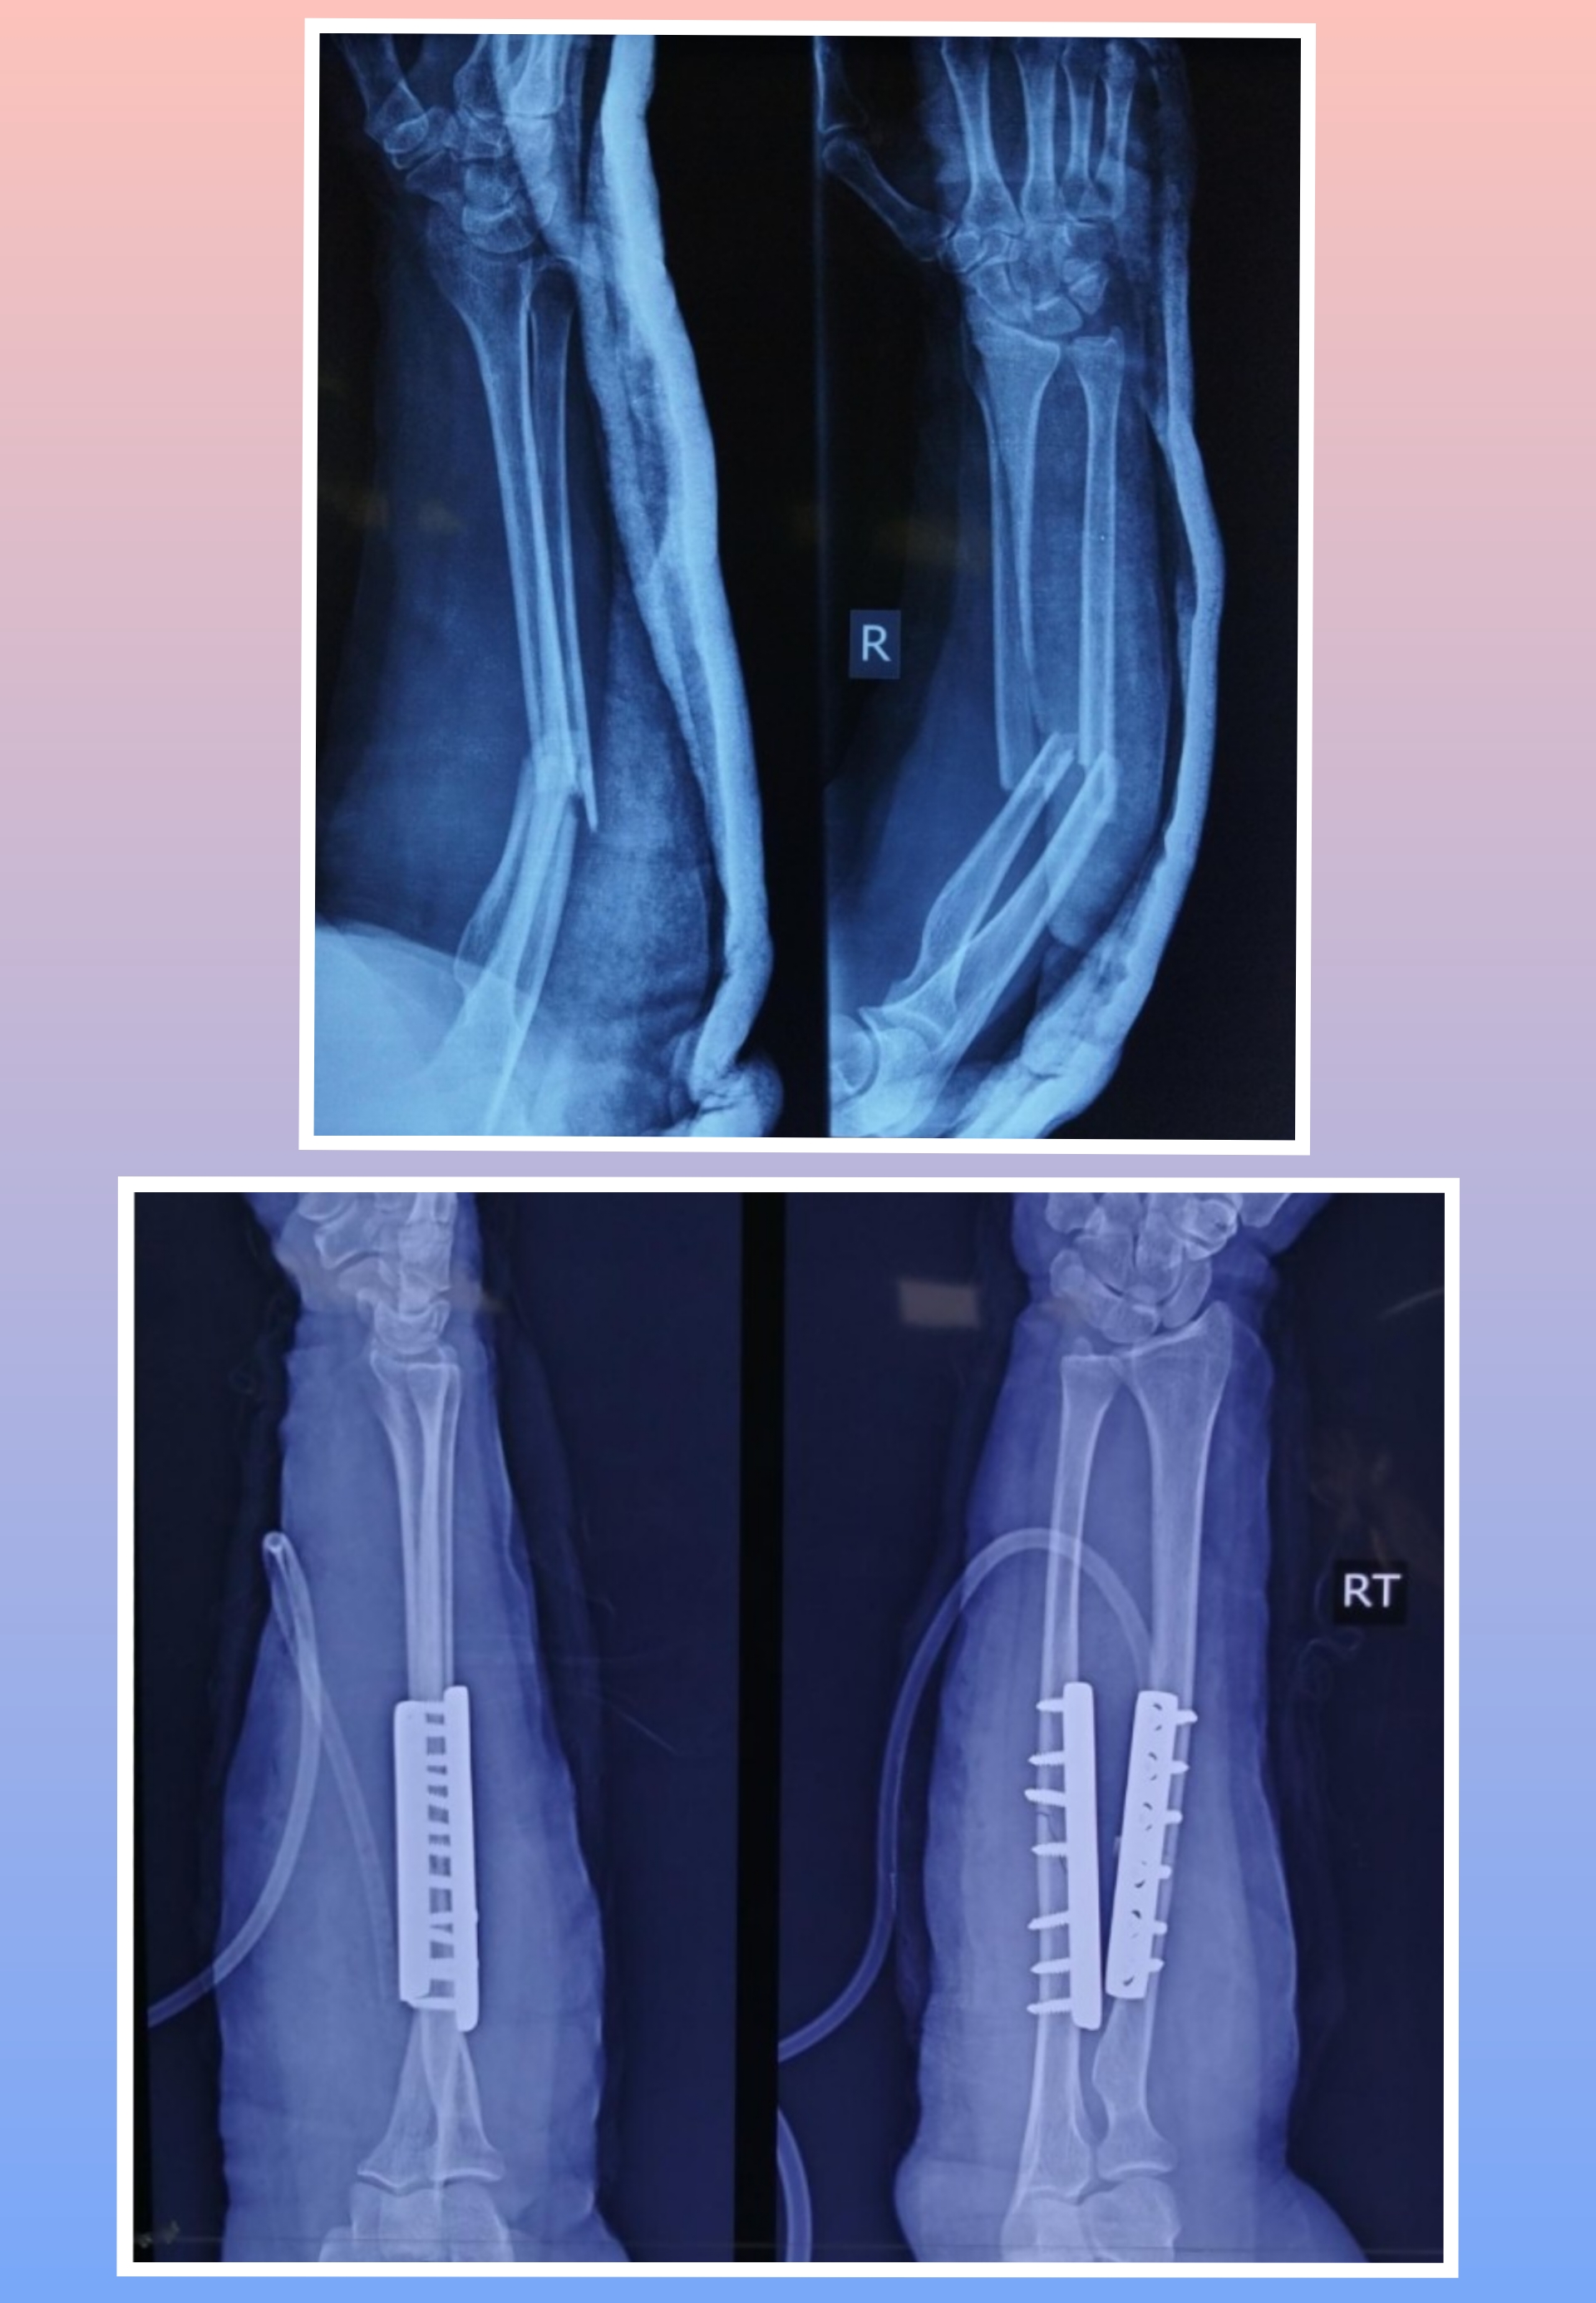

X-ray

Warning: Graphic Content

The following section contains graphic images of surgical procedures. These images are intended for educational purposes and may be disturbing to some viewers. Viewer discretion is advised.

Surgeries